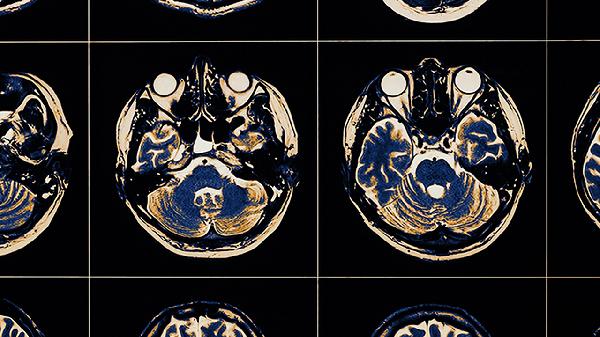

迟发性脑病最常见的表现

迟发性脑病最常见的表现包括认知功能障碍、运动障碍、精神行为异常、语言障碍和自主神经功能紊乱。迟发性脑病通常由一氧化碳中毒、脑外伤、脑血管疾病等因素引起,建议患者及时就医,在医生指导下进行针对性治疗。